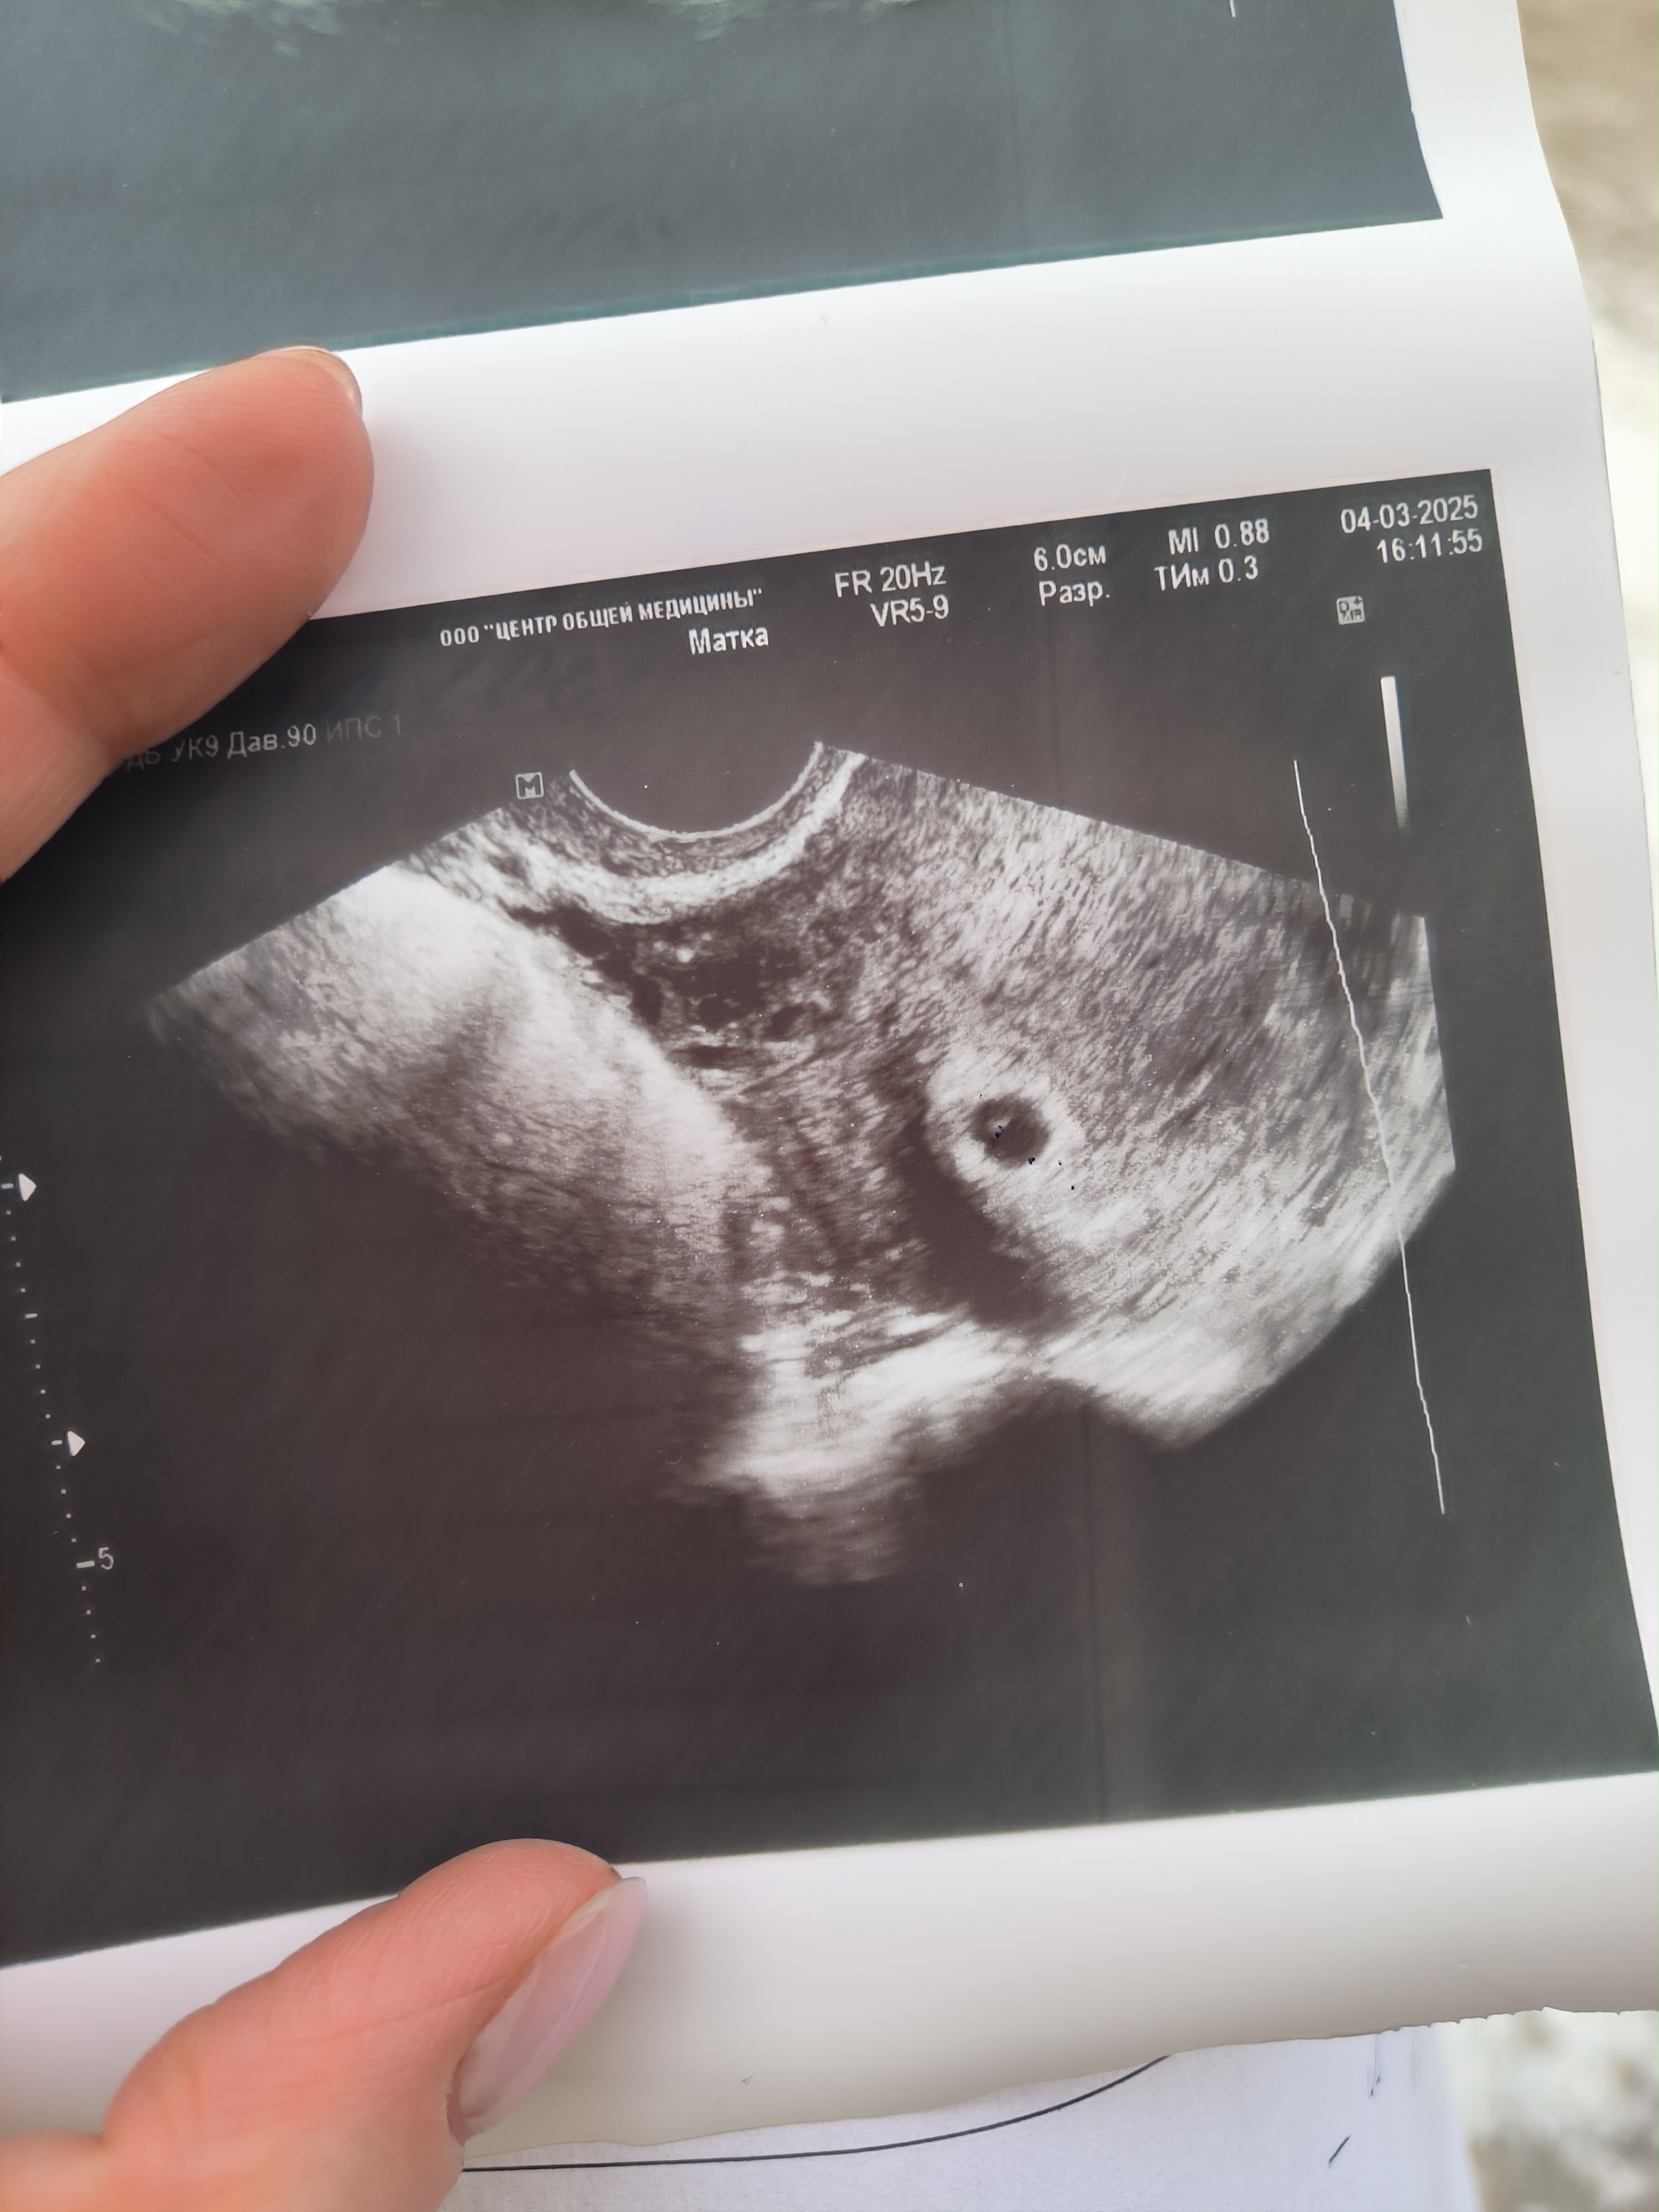

Кристина в Зачатие 9 месяцев Узи УЗИ 5 недель) наша точечка🥹 Сердцебиение ещё не было слышно, через 2 недели сказали повторить узи Иду уже в это воскресенье, будет 7 недель) Посмотрите еще 20 записей на эту тему Отменить Ответить Инга Не знаете какой хгч.? Я завтра иду, очень переживаю! Легкой беремености, растите здоровенькими) 11.03.2025 Ответить Кристина Инга, ХГЧ сдавала всего раз, когда тест // показал, тогда было 4 недели, 228 был результат, сейчас не знаю) Спасибо вам🙏 11.03.2025 Ответить Овуляция 2 раза в месяц 🤪 Резкое истощение яичников? Чаты Беременных Выберите чат: Январята-2026 Февралята-2026 Мартята-2026 Апрелята-2026 Майчата-2026 Июнята-2026 Июлята-2026 Августята-2026